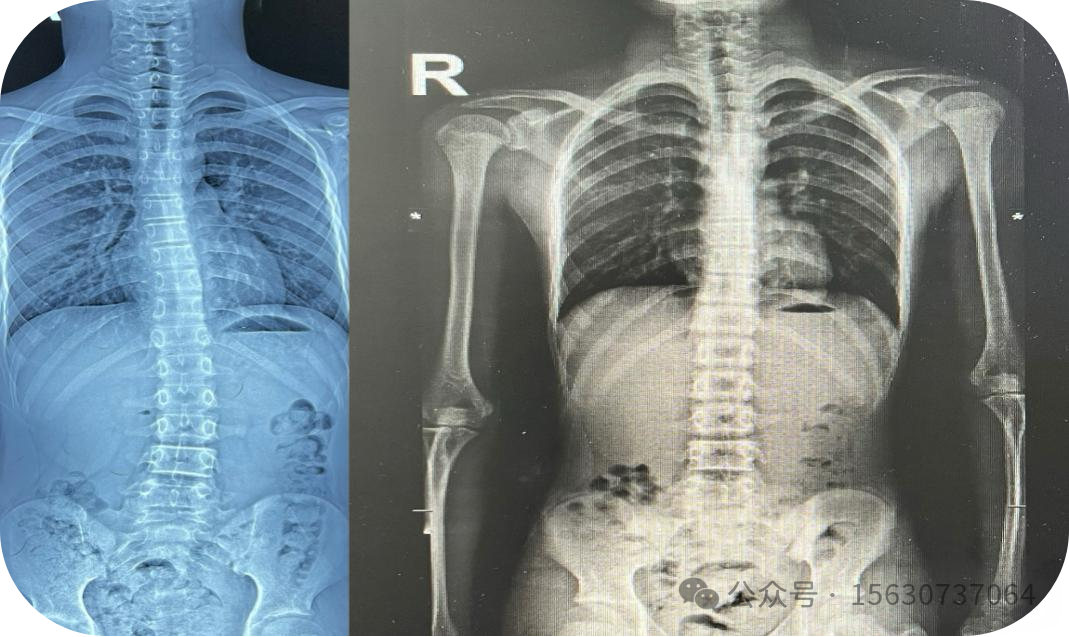

IDD结合康复治疗青少年脊柱侧弯影像对比图